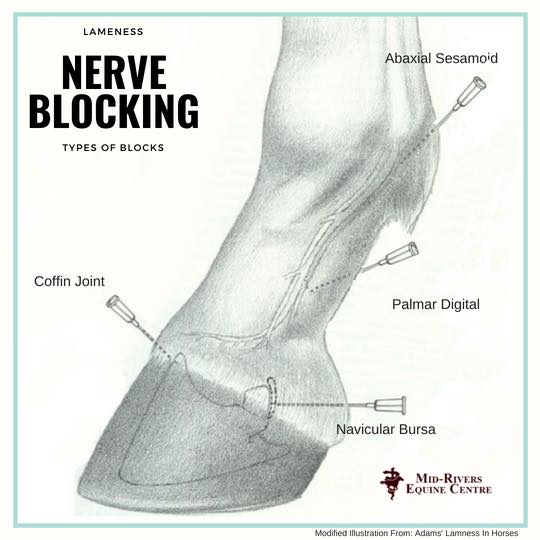

VET 2018 LAS Group E Lab 4 Equine Lameness – How does one investigate …

VET 2018 LAS Group E Lab 4 Equine Lameness – How does one investigate …